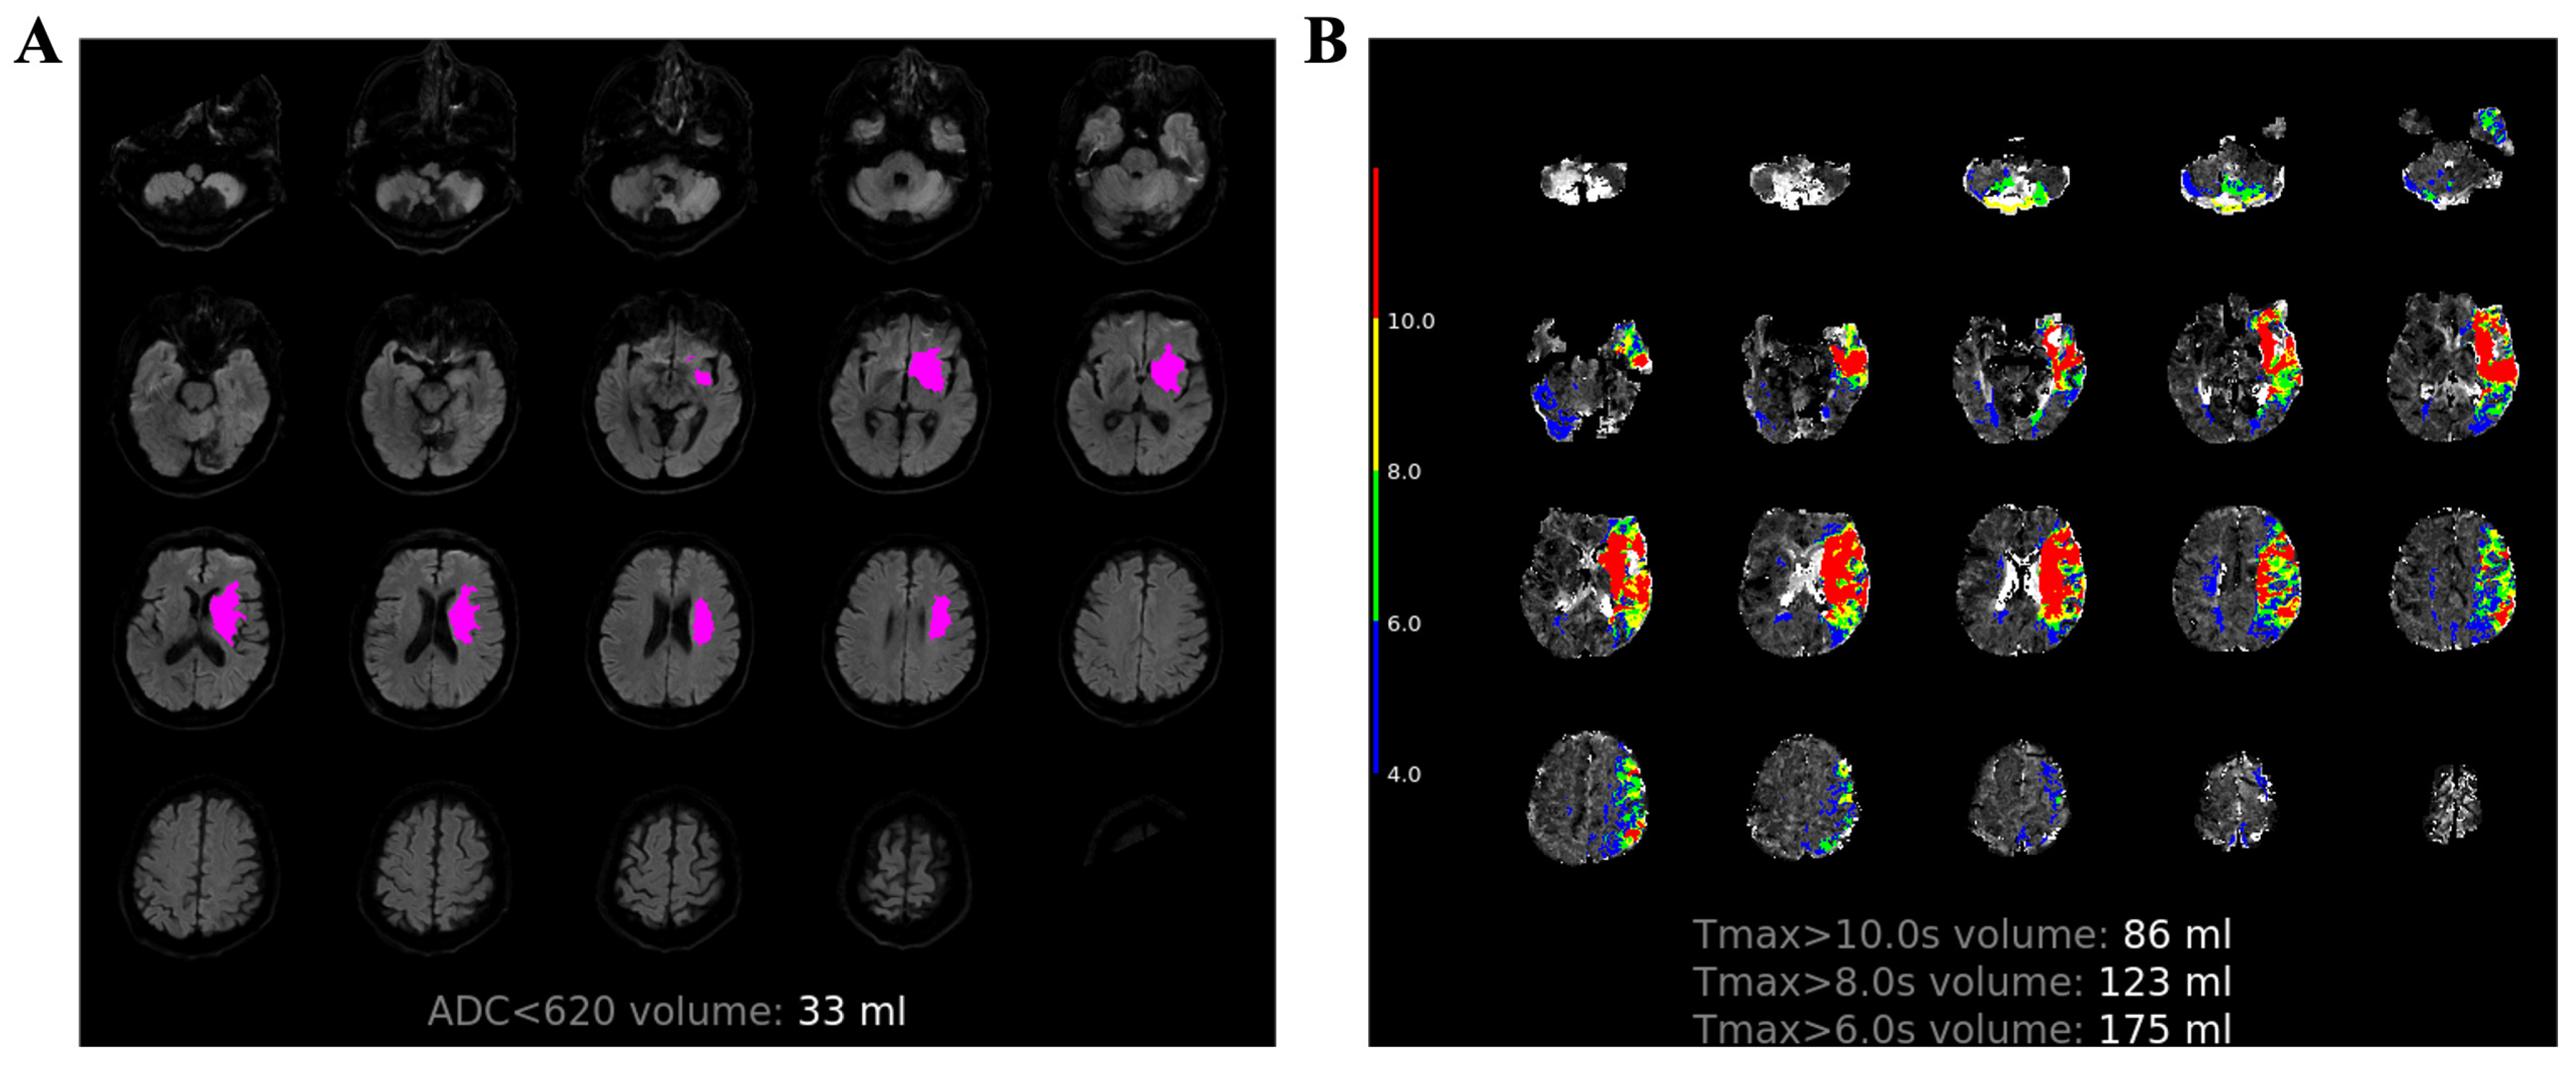

2.2. MR Protocol

2.3. Image Process

| ADC < 620 × 10−6 mm2/s (mL) | 5 (0–26.75) | 30 (8–91) | 0 (0–8) | <0.001 |

| Tmax > 6 s (mL) | 26.5 (0–123.75) | 141 (59–190) | 0 (0–37) | <0.001 |

| Tmax > 8 s (mL) | 7 (0–70.75) | 98 (33–137) | 0 (0–11) | <0.001 |

| Tmax > 10 s (mL) | 3 (0–40.5) | 71 (23–102) | 0 (0–4.5) | <0.001 |